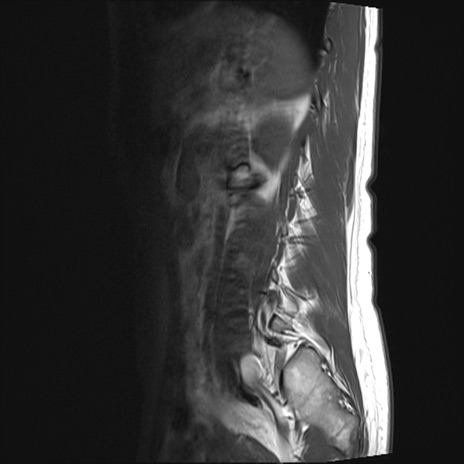

【整形】TIPS症例4 腰椎MRI T1WI(矢状断像)

腰椎MRI

STIR(矢状断像)